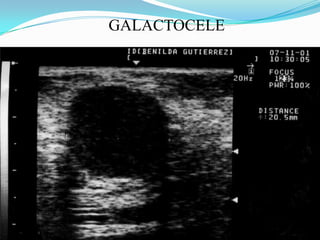

GALACTOCELEQUISTE MAMARIO  DE CONTENIDO LACTEONO HAY SIGNOS DE INFLAMACION O ABSCEDACION EN SU INICIOLAS MEDIDAS COMO CALOR MASAJE  LACTACION

GALACTOCELE